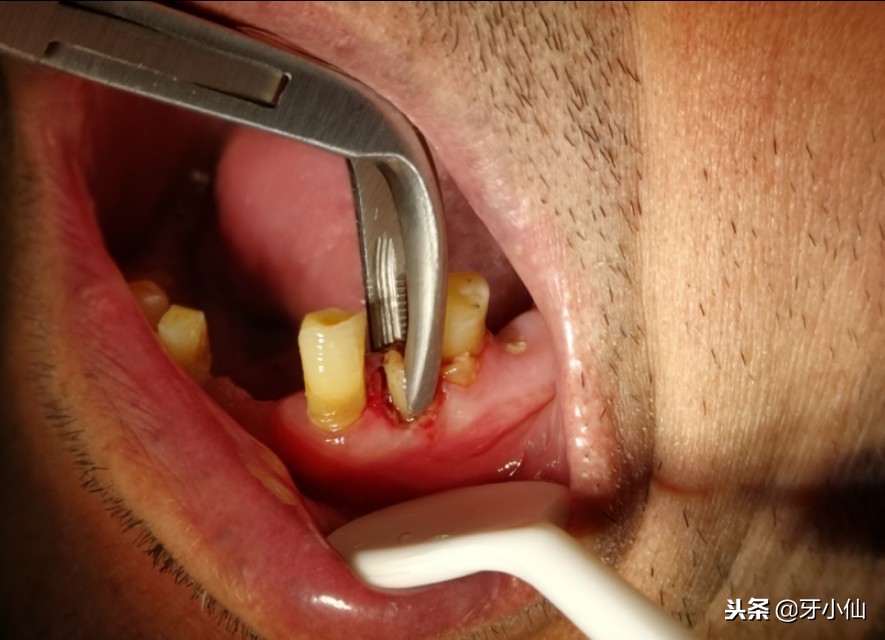

拔除的尖牙

拔牙前打麻药